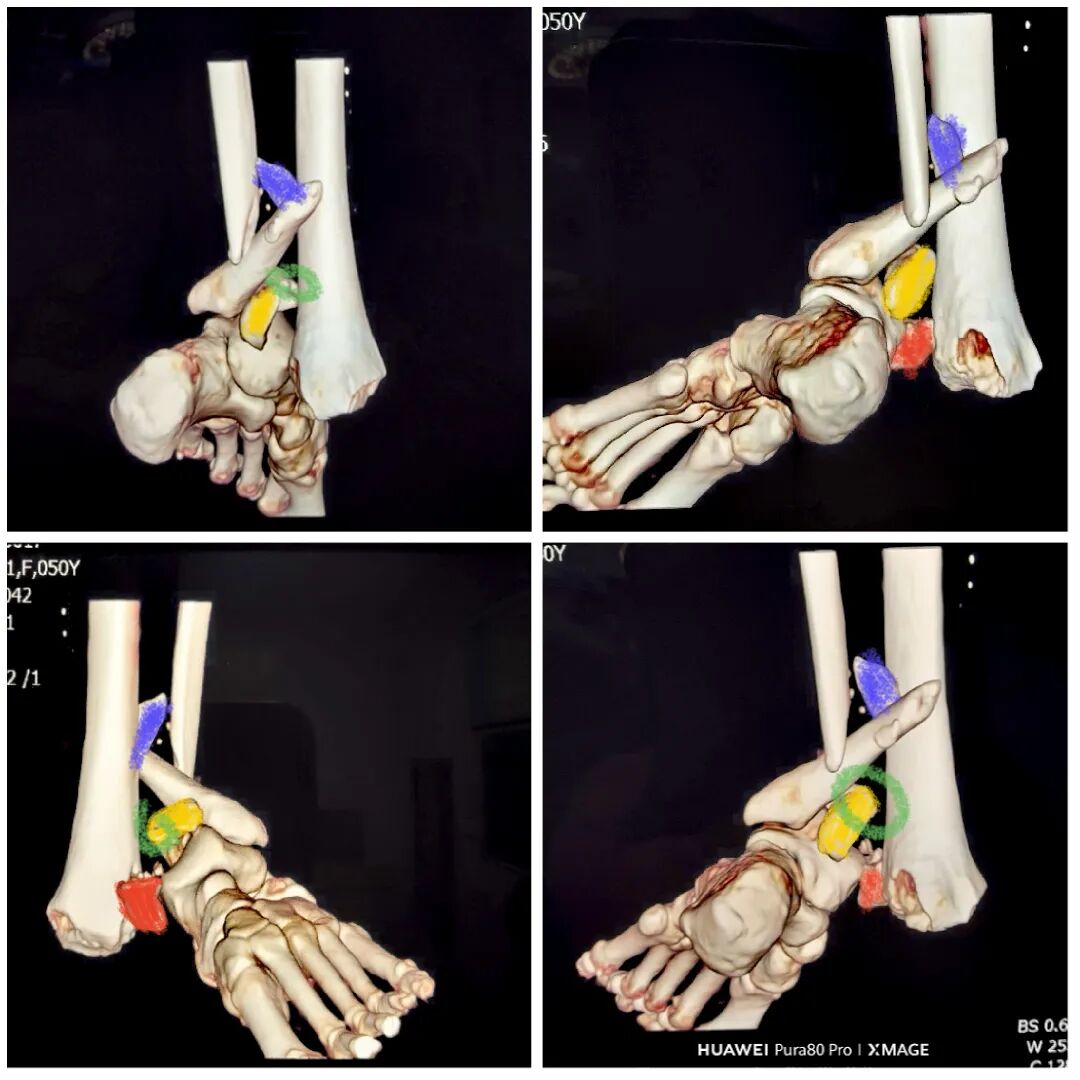

术后复查:

下胫腓关节复位良好

但前侧Chaput骨块

后侧volkmann骨块都移位